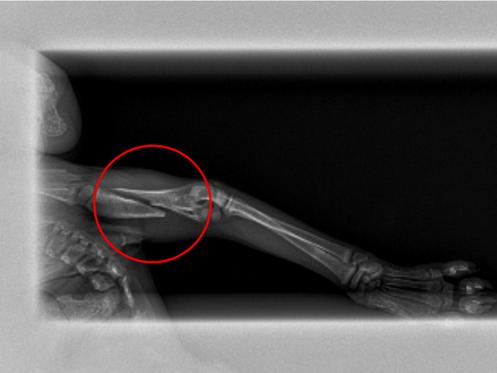

Oftentimes, homeless animals that come to AniMeals are in need of urgent care. Many suffer serious illnesses from neglect. Some have broken bones and/or life-threatening injuries. Most, if not all, critical care cases require specialized veterinary services that come with a premium price tag.

Little 6-week-old Diana was found taped inside of a diaper box with her littermates. During her intake exam, AniMeals staff noticed that she was not putting weight on her front left paw. An x-ray indicated that Diana was suffering from a complete spiral fracture and needed pins to heal her leg. The veterinary staff at Animal Blessings performed the surgery setting her on the road to a full recovery. When we asked, our community covered the $650 veterinary bill (and then some)!